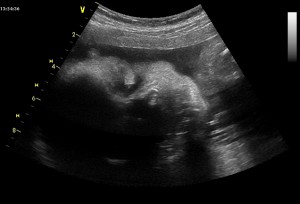

A tady podle té fotky poznali, že jsem chlapeček… to co je mírně vlevo od prostředka, to by měl být pindík a pod ním kousek nožičky, stehýnko a stehenní kost. Druhá nožička už není tolik vidět. Jestli to ještě někdo nevidí, tak jako další nápověda je, že jsem v poloze na zádech, mám hodně skrčené nožičky a vystrkuju zadeček…

Už to vidíte? Ale myslím, že bude nejlepší si počkat, až to uvidíte ve skutečnosti...